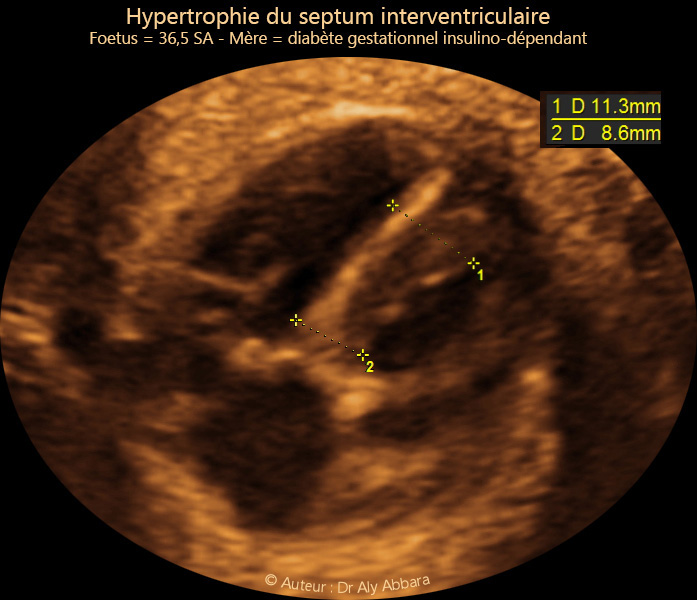

Hypertrophie du septum interventriculaire chez un foetus de 36,5  SA  et mère diabétique insulinodépendante

Images échographiques montrant une hypertrophie du septum interventriculaire (hypertrophie septale) qui mesure 8,6 mm pour une valeur normal à terme inférieure 6 mm.

Fœtus de 36 SA et 3 jours ; pesant à la naissance 3100 g (70° percentile).

Mère diabétique insulinodépendante ; il s'agit diabète gestationnel récidivant à chaque grossesse ; la grossesse actuelle est sa 4ème grossesse.

La mesure de l'épaisseur du septum interventriculaire, comme on le voit dans l'image ci-dessus, se fait en mode TM sous l'insertion des valves auriculo-ventriculaires et en diastole. La ligne de mesure TM est perpendiculaire au septum inter-ventriculaire.

Les valeurs normales de l'épaisseur septale dépendent de l'âge gestationnel, mais elles sont à moins de 6 mm à terme,